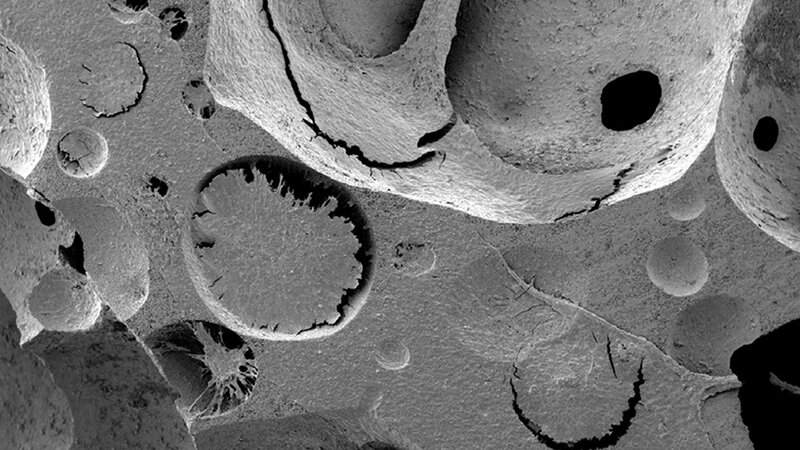

Die Stamm- und Vorläuferzellen konnten sich in der neuartigen künstlichen Knochenmarknische über mehrere Tage vermehren. Das Gewebe ahmt manche der komplexen biologischen Eigenschaften der natürlichen Knochenmarknischen nach. Die Wissenschaftler um Prof. Ivan Martin (Basel) und Prof. Timm Schroeder (Zürich) kombinierten dafür menschliche mesenchymale Stromazellen mit einem knochenähnlichen, porösen dreidimensionalen Gerüst aus Keramik in einem sogenannten Perfusions-Bioreaktor, in dem sich biologische und synthetische Materialien verbinden lassen.

So entstand eine Struktur, die von einer extrazellulären Matrix überzogen ist, in die sich Zellen einfügen können. In diesem Aspekt ist das künstliche Gewebe den natürlichen Knochenmarknischen molekular sehr ähnlich. In dieser Umgebung gelang es, die Funktionsfähigkeit von hämatopoetischen Stamm- und Vorläuferzellen weitgehend zu erhalten.